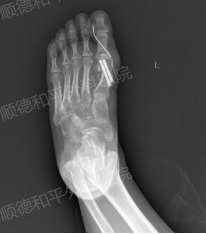

术后当天

术后第5天患者既已康复出院,经过术前的手术方案精心设计,以及术中、术后的用心治疗,患者恢复良好,对外形也很是满意,有效阻止了拇外翻的进一步发展。